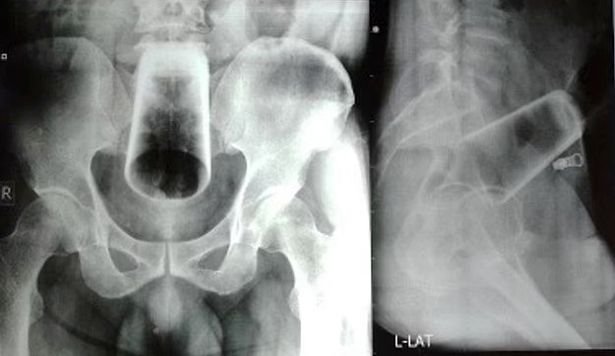

몸 속에 유리컵이 들어가 수술로 빼낸 네팔 40대 남성이 성적 의도로 일부러 넣었다고 실토했다. 의료진은 해당 수술 기록을 네팔전국의사협회에 보고하며 '항문을 통해 물체를 삽입하는 행동은 위험하다'고 경고했다. [사진출처=네팔의료협회]

의료진은 변비로 내원한 A 씨에게 특별한 외상 징후가 보이지 않자 엑스레이를 촬영했다. 이 과정 중 A 씨 골반 근처에 있는 유리컵을 발견한 것이다. 이에 의료진은 A씨와 면담을 요청했다.

의료진은 처음에는 외과적 수술 없이 직접 컵을 잡아 뽑으려고 했으나 컵이 너무 깊숙한 곳에 있었다. 이에 의료진은 결장절개술로 진행하기로 했다. 결장은 항문과 직접 연결된 동물의 최종 소화 기관이다. 수술을 통해 컵은 내장에서 안전하게 제거됐고 A씨는 수술 후 일주일 만에 퇴원해 회복한 것으로 전해진다.